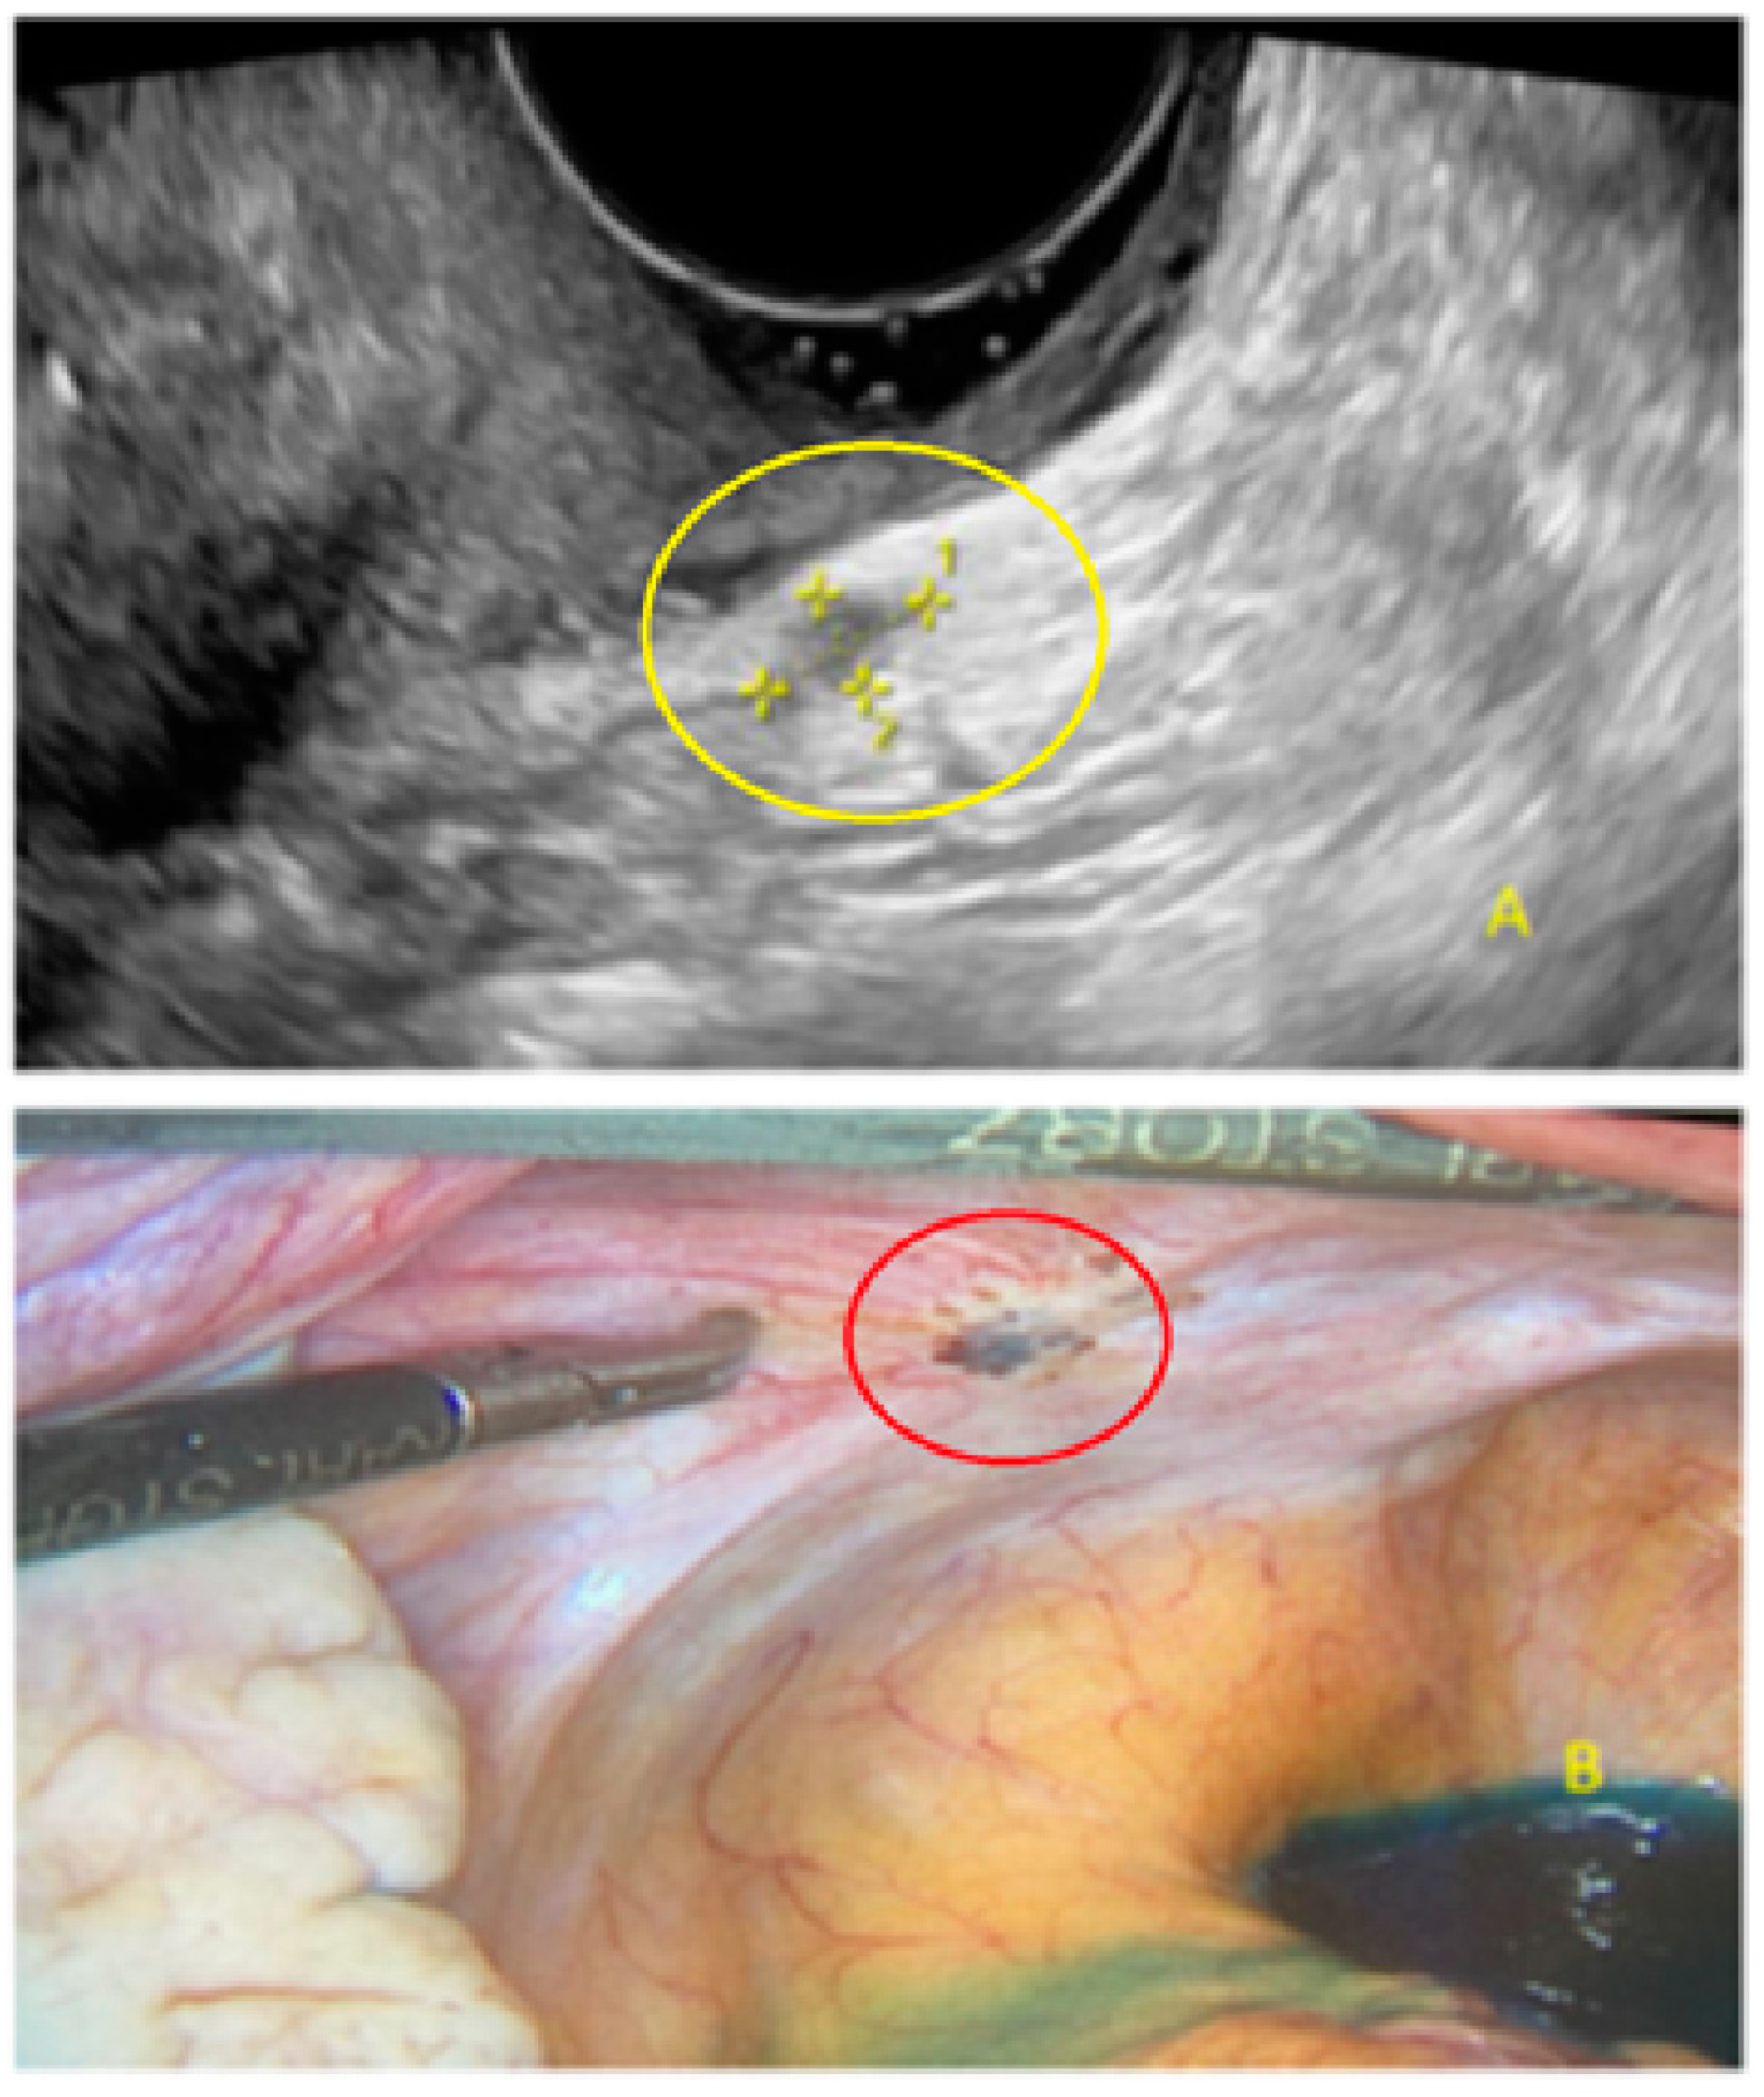

- The presence of hypoechogenic associated tissue (hypoechoic areas surrounding a small cyst area; we called this a “hat”). This tissue does not protrude or invaginate the peritoneal surface.

- The lesion may be convex, protruding from the peritoneal surface into the peritoneal cavity (we called this “bulging”), or it may appear as a concave defect in the peritoneum (we called this a “pocket”).

- The presence of hyperechoic foci (we called this a “pearl”).